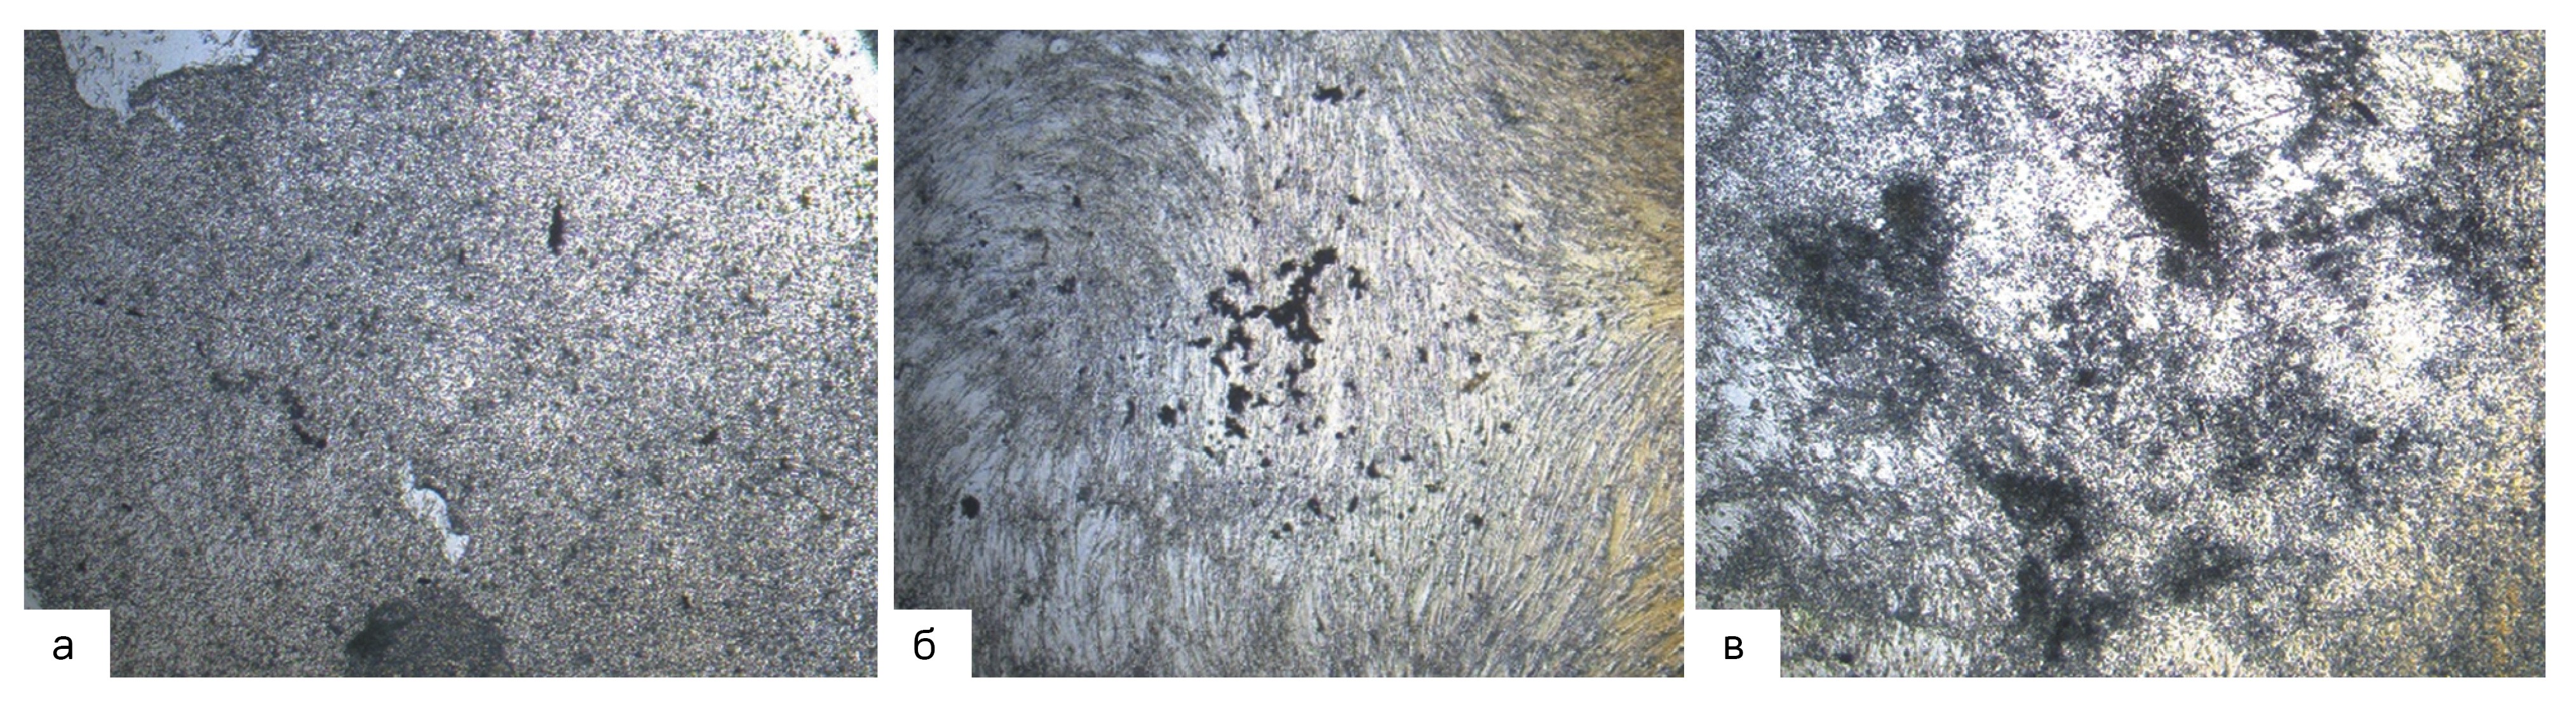

In the period from the 4th to the 7th day of cultivation in the OM (including addition of alPRP), there occurs re-differentiation of BM-MSC. In this period, the cells start expressing osteogenic markers, yet no calcium deposition starts in them. After 21 days of osteogenic differentiation, it was shown that the morphology of BM-MSC changed from spindle to cuboid. After Von Kossa’s staining of the specimens of differentiated cells with nitrate of silver, additionally, intracellular deposits of calcium phosphate were found (stained black). The changes were most manifested in the cells cultivated in the OM with 5% alPRP added (Fig. 4).

Figure 4. Von Kossa staining of BM-MSCs: (a) cells cultivated in CCM; (b) cells cultivated in OM; (c) cells cultivated in OM, supplemented with 5% alPRP. Images are taken at 100x magnification.

Рисунок 4. Окрашивание фон Косса КМ-МСК человека: (a) клетки, культивированные в ППС; (b) – клетки, культивированные в ОС; (c) – клетки, культивированные в ОС с добавлением 5% алПОРФТ. Изображения сделаны при 100-кратном увеличении.